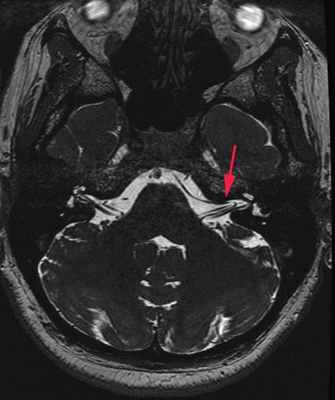

МРТ головного мозга пациента с ВП:

МР-признака вазоневрального конфликта между правой передненижней мозжечковой артерией

и правым преддверно-улитковым нервом (красная стрелка).